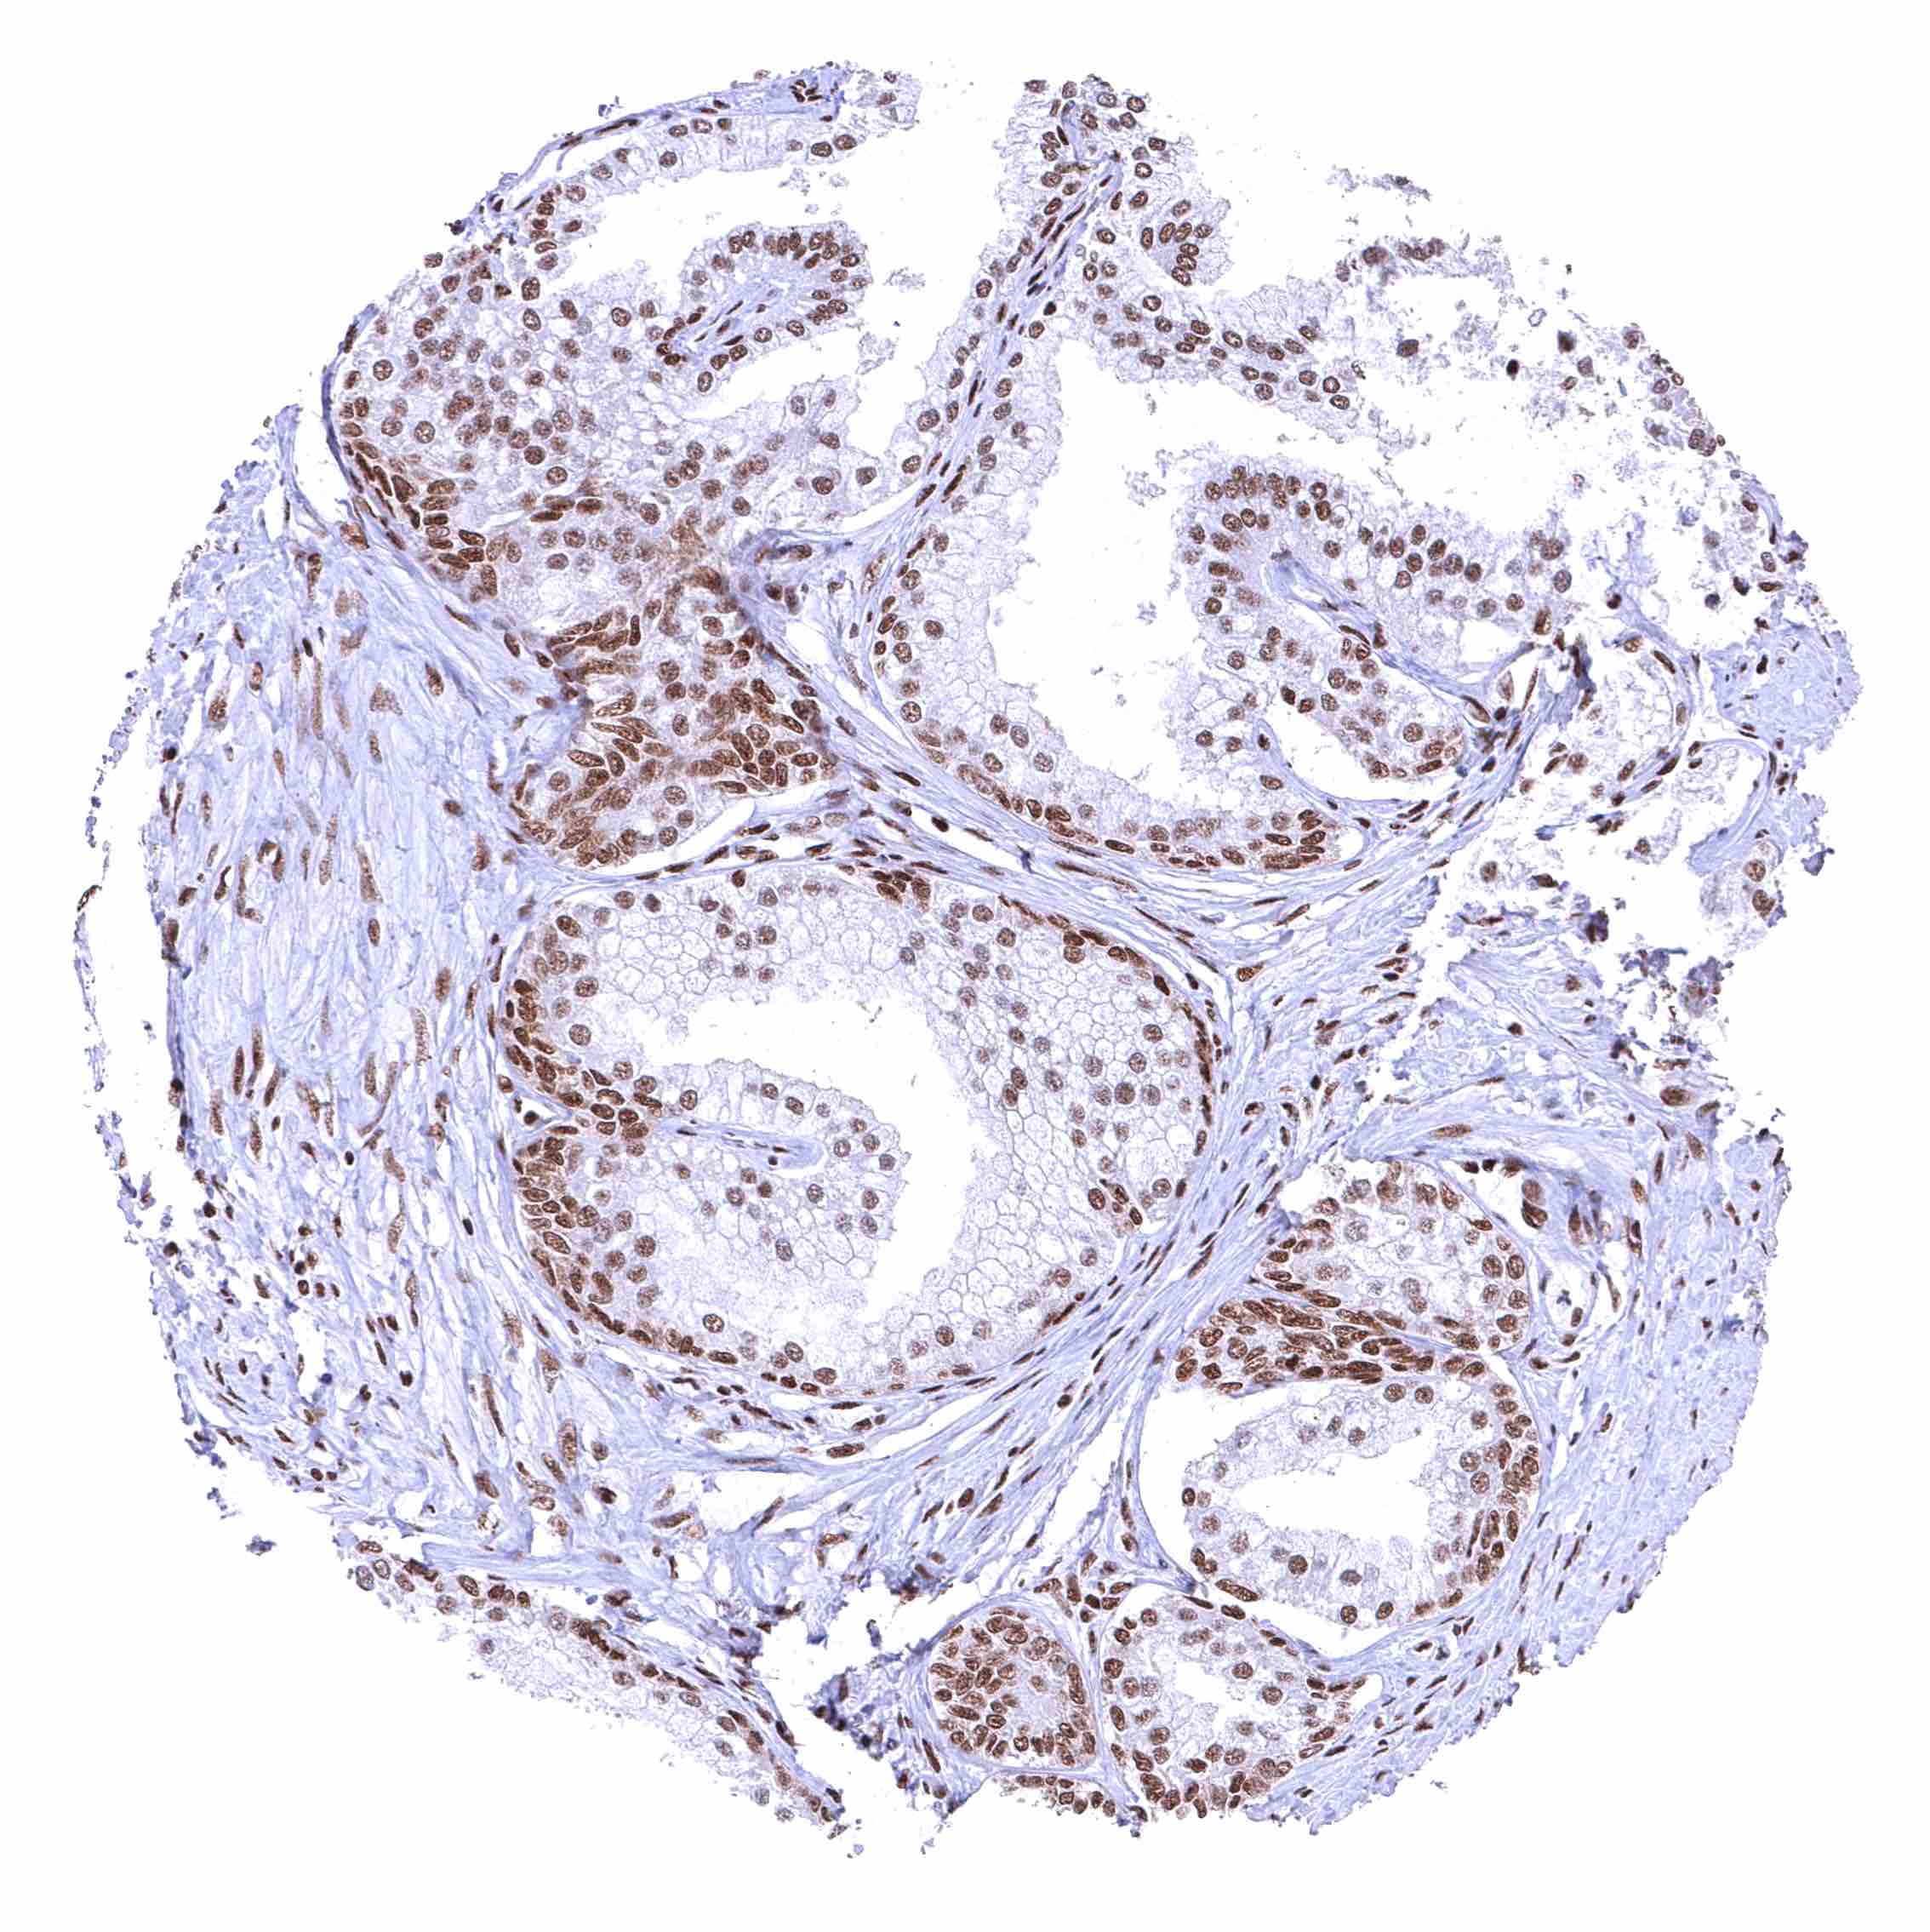

Fallopian tube, mucosa – Strong nuclear BRD4 staining of epithelial cells.